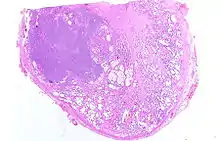

Adénocarcinome prostatique

Anatomopathologie

Le cancer entreprend la portion périphérique de la glande, au contraire de l'hypertrophie prostatique bénigne qui intéresse la zone centrale, périurétrale.